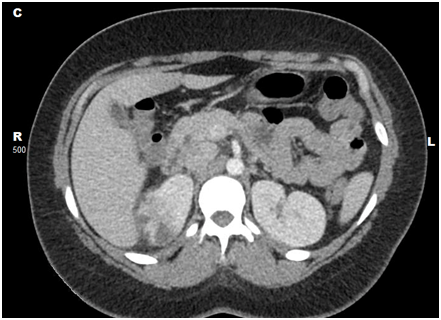

On follow-up as outpatient, she had recovered completely and renal ultrasound(Figure 2) at 4 weeks post discharge from hospital showed resolving changes of pyelonephritis.

Figure 2 Renal ultrasound of the case 1 after one month showing some radiological improvement but not completely disappearance of the hypoechoic area.